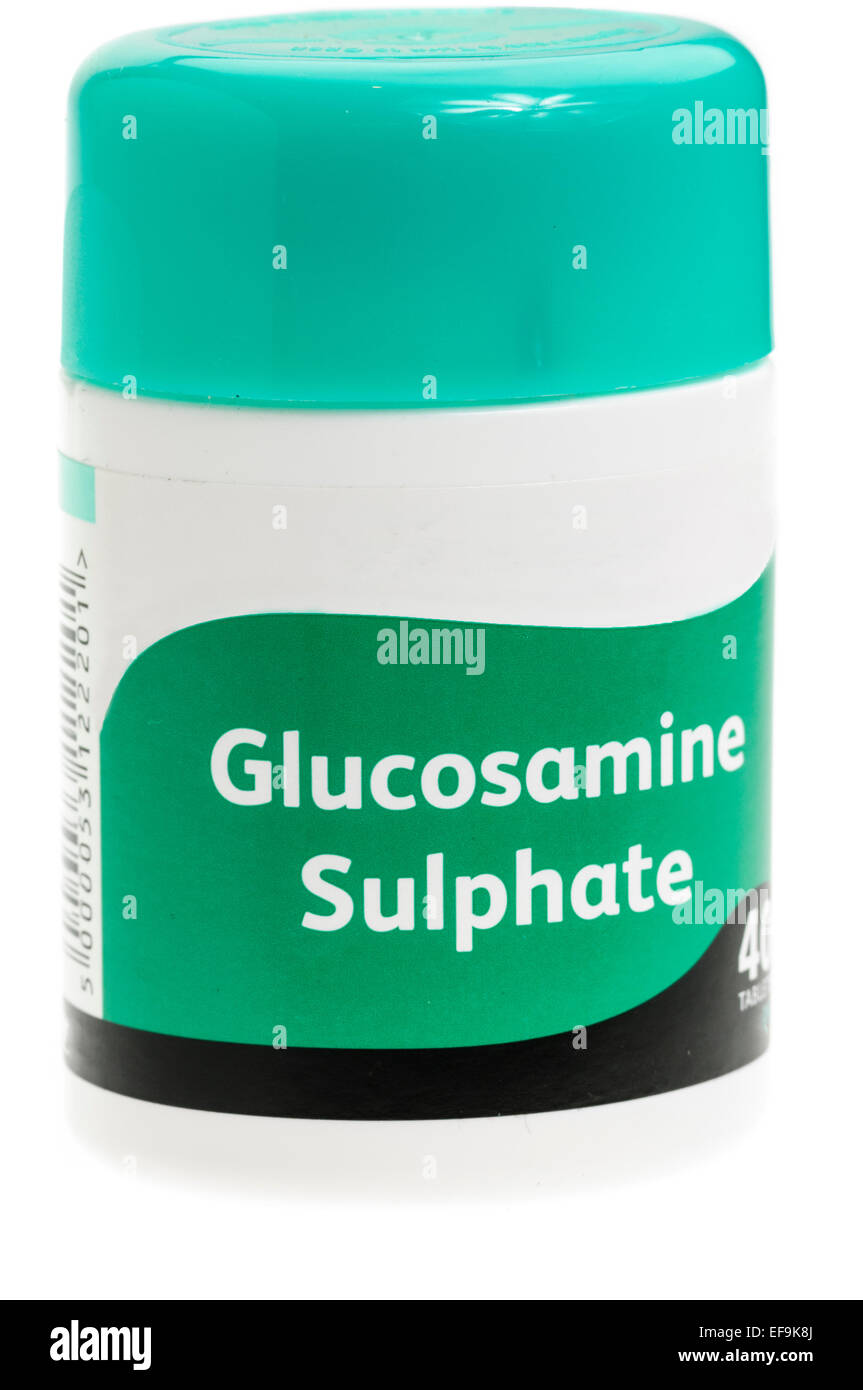

Bottle of Glucosamine Sulphate tablets, a supplement taken to relieve symptoms of arthritis. Stock Photohttps://www.alamy.com/image-license-details/?v=1https://www.alamy.com/stock-photo-bottle-of-glucosamine-sulphate-tablets-a-supplement-taken-to-relieve-78274018.html

Bottle of Glucosamine Sulphate tablets, a supplement taken to relieve symptoms of arthritis. Stock Photohttps://www.alamy.com/image-license-details/?v=1https://www.alamy.com/stock-photo-bottle-of-glucosamine-sulphate-tablets-a-supplement-taken-to-relieve-78274018.htmlRFEF9K8J–Bottle of Glucosamine Sulphate tablets, a supplement taken to relieve symptoms of arthritis.